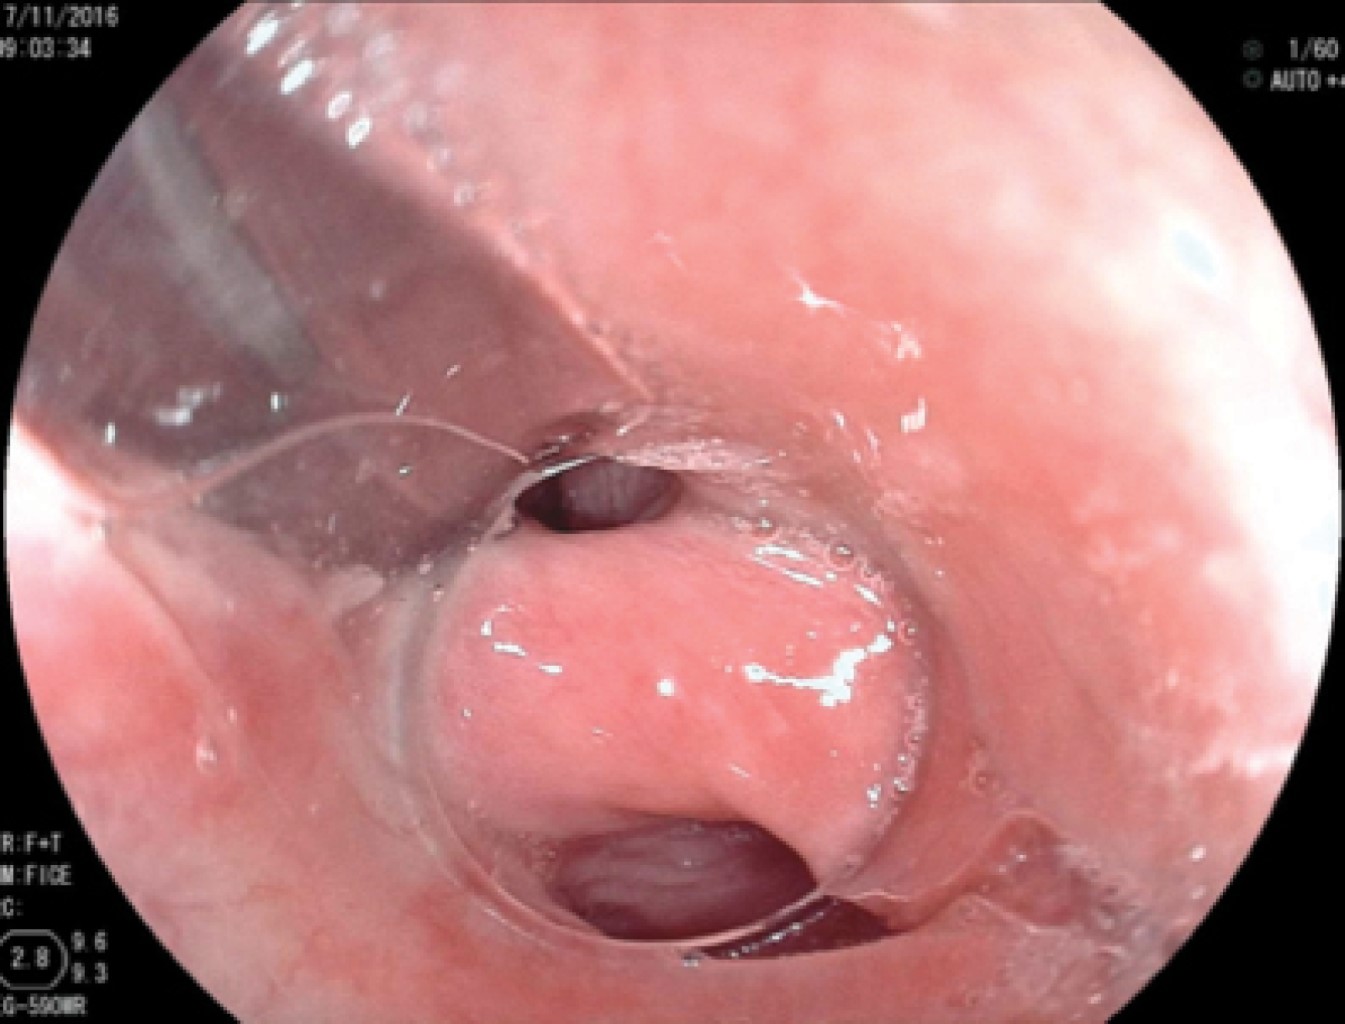

En los primeros 10 pacientes una vez identificada la luz del esófago, se introdujo una guía metálica a la cavidad gástrica y sobre ésta un dilatador de Savary Gilliard de 7 mm o 21 Fr, el cual llega hasta el estómago y se deja en ese sitio. Lo anterior delimita adecuadamente la luz del divertículo y del esófago (Figura 2). En el extremo distal del tubo de inserción del endoscopio se coloca un capuchón plástico transparente (MBL 6-1 Cook Endoscopy) que se utiliza como espaciador, lo que permite identificar el septum del músculo cricofaríngeo. En los primeros 10 casos se utilizó un videogastroscopio Olympus modelo GIF-H140 y procesador de imagen CV-140 Olympus (Olympus Optical Co., Tokio, Japón) de 9.8 mm de diámetro, la unidad electroquirúrgica Olympus UES-40 SurgMaster, y como disector un cuchillo aguja (Needle Knife, Cook Endoscopy, Winston-Salem, NC), se hace un corte en el borde de la luz esofágica en la parte media del septum y hacia la luz del divertículo. Se realiza primero el corte de la mucosa exponiendo las fibras musculares del cricofaríngeo (Figura 3), el corte se profundiza hasta completar la sección de las fibras transversales del esfínter cricofaríngeo, sin necesariamente llegar al fondo del divertículo (Figura 4), lo que permite la aproximación de los bordes de la incisión en la mucosa con clips metálicos evitando la perforación y riesgo de sangrado (Figura 5). A los cuatro pacientes restantes se les aplicó la técnica de POEM (miotomía endoscópica peroral), infiltrando la submucosa con solución fisiológica y azul de metileno para levantar la mucosa, posteriormente, se corta la mucosa con el hidrodisector HybridKnife, tipo T-type marca ERBE que es un instrumento multifuncional que combina tecnología electroquirúrgica e hidrodisección en un solo instrumento con el cual se realiza un levantamiento de la mucosa y la creación de un túnel submucoso, seccionando sólo las fibras musculares transversales y finalmente cerrando la entrada del túnel con clips endoscópicos. En estos pacientes se utilizó un videogastroscopio Fujinon, procesador de imágenes Fujifilm Processor VP-4450HD, unidad electroquirúrgica ERBE VIO 200 D y el HybridKnife de ERBE, T-type (marcas registradas) utilizando corriente de corte y coagulación pura (50 W). Por último se retira el dilatador de Savary Gilliard y posterior al procedimiento se efectuó un trago de material hidrosoluble para descartar fugas. A todos los pacientes se les administró una dosis única de antibiótico al inicio del procedimiento y fueron manejados de forma ambulatoria en domicilio iniciando con dieta líquida a las cuatro horas.

Se realizaron en total 18 procedimientos, se consideró como complicación sólo un paciente (7.1%), quien presentó sangrado importante, mismo que se controló, pero impidió en el procedimiento inicial completar adecuadamente la miotomía, por lo que se reintervino a las 24 horas para completar ésta. Durante los procedimientos, dos pacientes tuvieron enfisema subcutáneo (un paciente femenino de 74 años y uno masculino de 57 años), los cuales fueron tratados de forma conservadora mediante la administración de una cefalosporina de tercera generación, así como control radiográfico para medición del enfisema subcutáneo (Figura 6). No se presentaron complicaciones mayores como mediastinitis, hemorragia incoercible o perforación que requirieran cambiar el tratamiento endoscópico por el quirúrgico de urgencia o programado. La mejoría de la disfagia en todos los casos fue inmediata y en las consultas subsecuentes refirieron haber aumentado de peso, además se realizó endoscopia y trago de material de control (Figura 7).

Figura 7